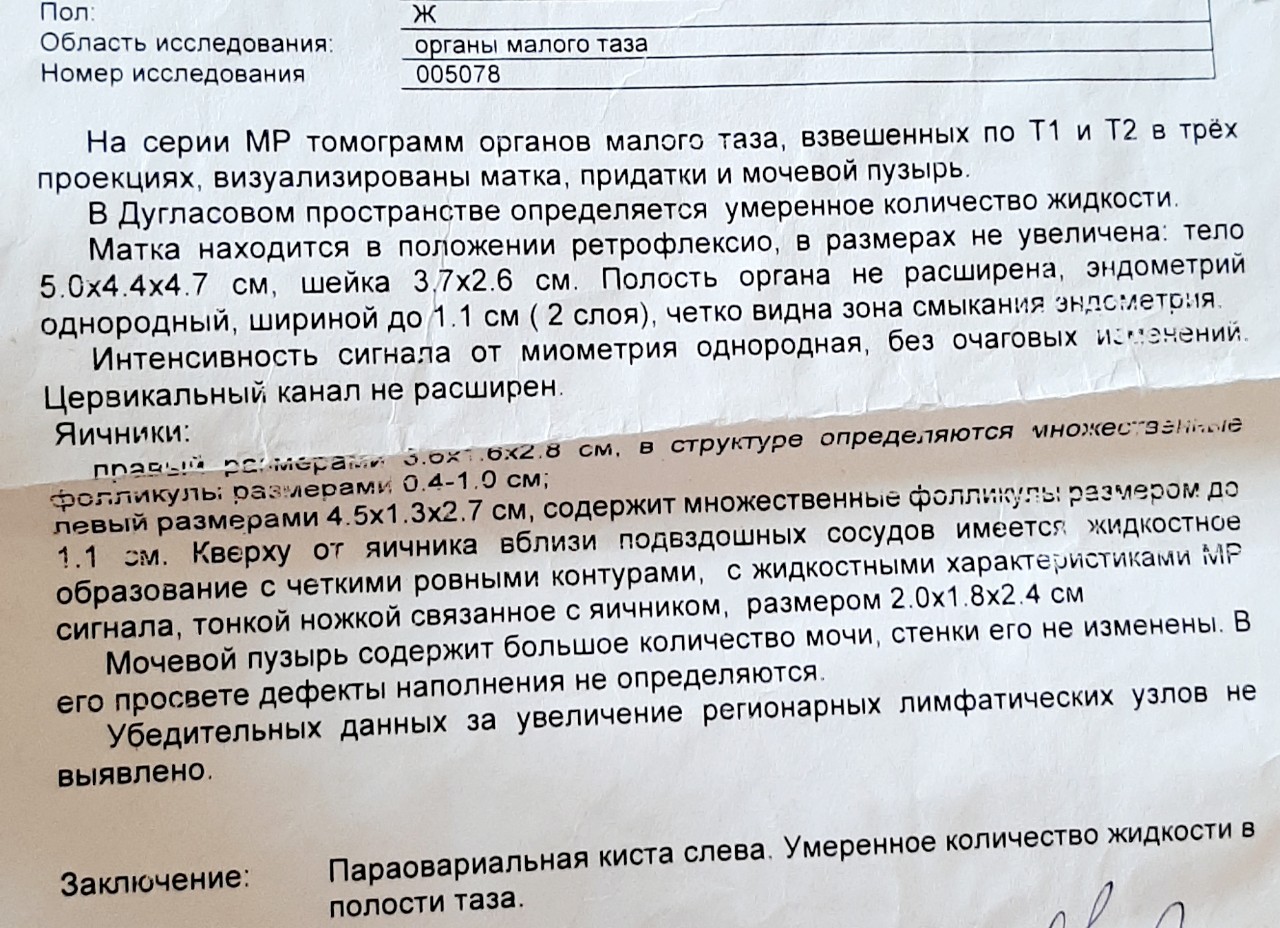

Снимки мрт ОМТ

Примеры фото МРТ малого таза у женщин

Ниже представлены примеры фотографий МРТ малого таза у женщин, позволяющие увидеть, как выглядят снимки и какие изменения могут быть обнаружены специалистами.